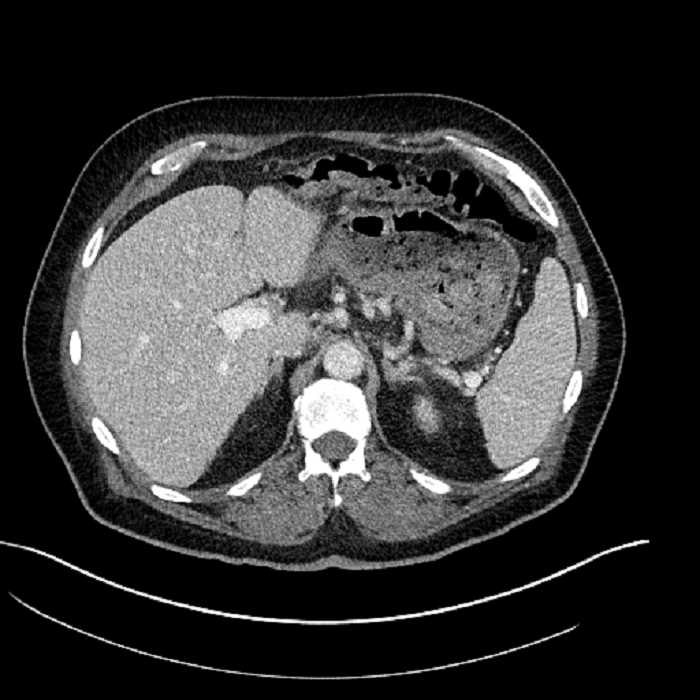

• Large fluid density structure in hepatic segments 7 and 8 measuring 10 x 7 x 7 cm with internal septation and circumferential ill-defined low density compatible with edema

• Peripherally enhancing subcapsular collections along the anterior margin of the left hepatic lobe measuring 3 x 1 cm and 2 x 1 cm

• Clearly marginated fluid density structure in segment 7 and several other scattered tiny hypodensities, which likely represent cysts

Acute sigmoid diverticulitis complicated by a small contained perforation and a large abscess in the right hepatic lobe. Additional small subcapsular abscesses along the anterior margin of the left hepatic lobe.

• The classic CT imaging appearance is a double target sign with internal low density surrounded by an internal enhancing rim (capsule) and a low density external rim (edema)

Hepatic abscess showing the double target sign with low density internally surrounded by a thin inner enhancing rim (red arrow) and ill-defined outer low density rim (yellow arrow). Blue arrow indicates an internal septation. Red arrows: additional smaller subcapsular abscesses. Red arrow: focal contained perforation associated with diverticulitis.